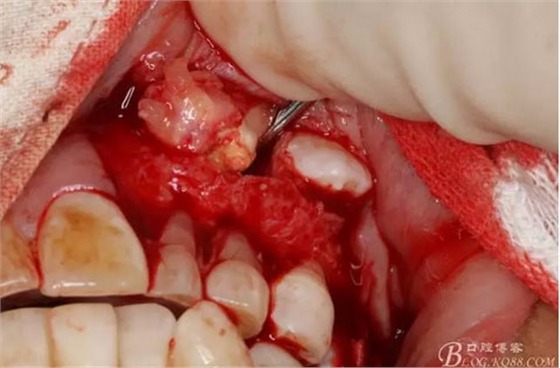

圖12.用小骨鑿去除覆蓋在牙瘤表面的骨質(zhì)。發(fā)現(xiàn)牙瘤的包膜。

圖13.暴露出部分牙瘤

圖14.沿一側(cè)骨壁逐步剝離牙瘤組織。

圖15.剝離出來的多個成型小牙齒及致密鈣化物。

圖17.呼之欲出的巨大牙瘤組織。